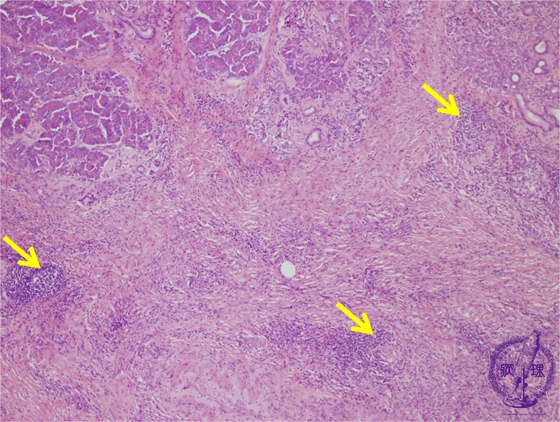

- (5)Chronic pancreatitis

Microscopic image(HE stain, low power): Advanced fibrosis is seen within the pancreatic parenchyma and interlobular spaces. Lymphoid follicles are seen forming amongst the fibrosis (arrows).